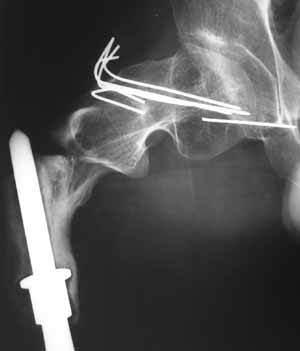

Уважаемые коллеги!У нас наблюдается пациент, 22 лет.В 1993 году -субтотальная резекция бедренной кости (остеогенная саркома -по выписке), установленэндопротез коленного сустава.

В 1998 году - перелом шейки бедра- оперирован в детской больнице (остеосинтез пучком спиц). В 2001 году- подвертельный перелом (полгода в коксите- сращение). В марте этого года- повторный подвертельный перелом (см RG). В настоящее время в коксите. Что дальше? Облздрав выделяет на лечение чуть более 100 тыс руб. (квота) Может кто-нибудь помочь пациенту? С уважением Ганин Алексей.

In 1998 - fracture of the femoral neck, was fixed by wires in ped ortho unit, healed.

In 2001 subtroch fracture, 6 months in plaster casr - healing was reached.

March 2004 - a new fracture at the place, images attached. Now the patient is in the cast again.

"subtotal resection of the femur for osteosarcoma" How much femur was removed or left? It's hard to tell from the radiographs.

Is the intramedullary device seen on the AP radiograph of the hip a component of the total knee replacement or something else?

A cable plate could provide stabilization of the remaining fractured proximal femur. Fixed angle device proximally (blade, screw or locking plate) with distal fixation of the plate to the bone/bone replacement prosthesis by means of cables. If there is bone in the subtrochanteric region (hard to see on the radiographs) then unicortical screws might also be possible. Of course, remove the wires in the femoral neck and head.

Создается впечатление, что причиной повторного подвертельного перелома бедра является нестабильность протеза( сложно судить о тибиальном компоненте по Рг грамме, но видимая часть бедра - на всем протяжении зона остеосклероза с истончением кортикала) Нестабильное *железо* вызывает резорбцию кости, ее ослабление и как результат -перелом ( обычно на уровне верхушки ножки протеза - зона стресса).